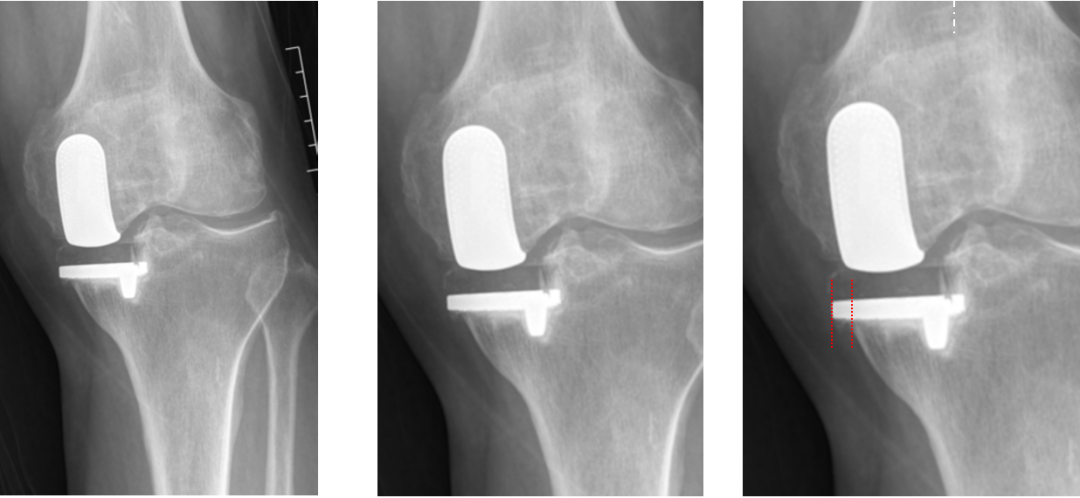

正位片标准胫骨和股骨假体位置

AP位假体位置:胫骨假体无内外翻,内侧缘超出胫骨平台内侧缘1mm; 股骨假体长轴与胫骨假体垂直,中线一致。

侧位片标准胫骨和股骨假体位置

侧位片假体位置:胫骨假体后倾3°,与胫骨平台前后缘齐平,股骨假体后倾40°,假体后缘与股骨后髁齐平。

胫骨假体厚度合适

胫骨垫片厚度合适:术前内翻畸形基本矫正,残留2-3°内翻。

股骨假体偏内放置,胫骨假体偏大

AP位胫骨与股骨假体位置:胫骨假体内侧悬挂>2mm,股骨假体中轴线与胫骨假体中线不一致,偏内侧。

股骨假体偏大且过度屈曲

侧位片假体位置:股骨假体后倾45°,假体后缘超出股骨后髁3mm, 胫骨假体后倾3°,与胫骨平台前后缘齐平。